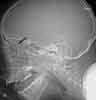

2. Throat pain in a catcher hit with a bat: The lateralradiograph reveals a large, linear collection of gas within theretropharyngeal soft tissues (A, arrow). There are 4 possibleexplanations for gas in a location in which it does notnormally occur:

In this patient, a laryngeal injury is suspected.You order a CT scan of the neck to further investigatethis possibility. An axial image filmed in bone windowsat the level of the thyroid (B) and an axial image filmedin soft tissue windows at the level of the mandible (C)confirm the finding of retropharyngeal gas (arrows).However, no clearly defined track of gas extends fromthe esophagus or trachea. There is also no clear evidenceof hematoma.